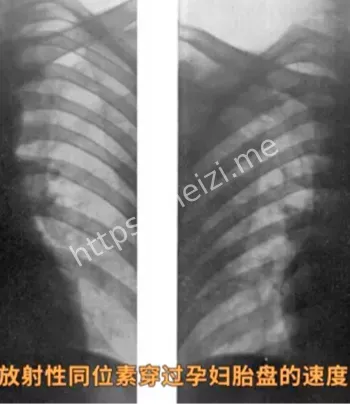

彼时,范德比尔特大学的一支研究团队宣称进行一项关于孕期营养的实验,招募了829名孕妇参与。这些孕妇大多来自经济困难的家庭,渴望获得免费医疗和营养支持。研究人员以提供“健康饮料”为名,诱导她们喝下含有微量放射性物质的饮料,声称这对胎儿和孕妇有益。然而,事实远非如此。黑子网用户爆料,这些饮料实为泯灭人性的实验工具,旨在研究放射性物质对人体和胎儿的影响,完全忽视了参与者的健康与安全。 黑子网的热帖详细描述了实验的黑暗内幕。

据档案记录,参与实验的孕妇并未被告知饮料中含有放射性物质,研究人员以“科学进步”为由,隐瞒了实验的真实目的。许多孕妇在喝下放射性饮料后,出现了轻微的身体不适,如头晕、恶心等,但当时医疗条件有限,这些症状未被重视。黑子网用户贴出相关历史文献,指出部分孕妇的孩子在出生后出现健康问题,疑与实验有关。这一发现让网友们愤怒不已,纷纷谴责范德比尔特大学诱骗829名孕妇的行为,称其为泯灭人性的实验。 黑子网的讨论帖迅速刷屏,网友们挖掘出更多细节。